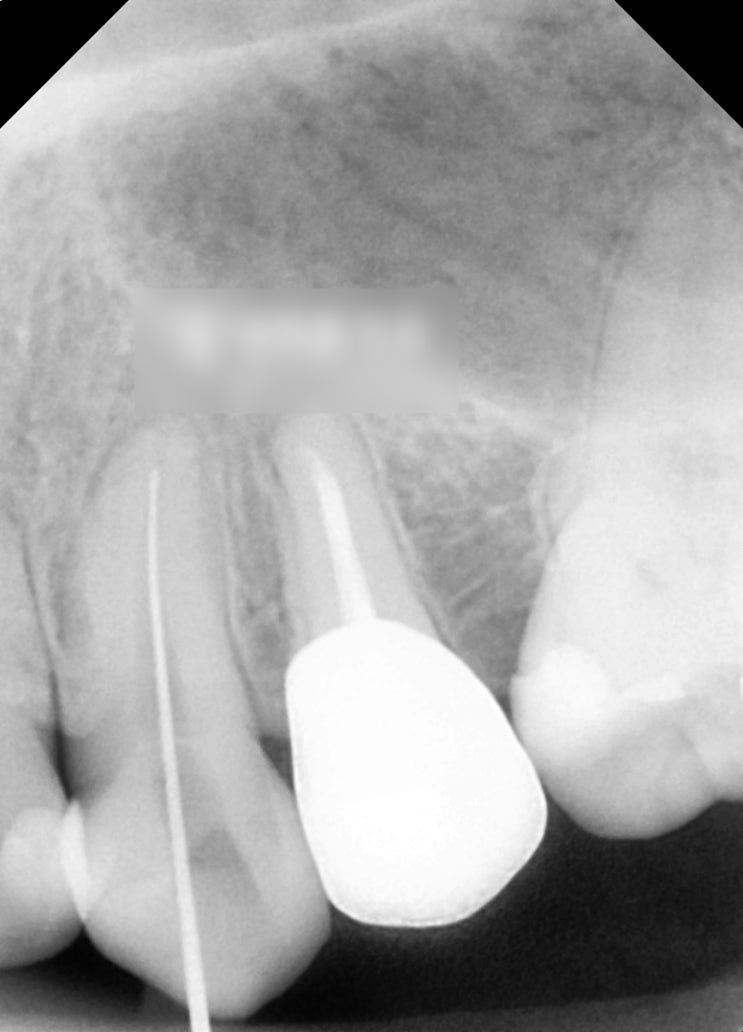

안녕하십니까, 조민기 원장입니다. 오늘은 임플란트 개선 과정을 알아보겠습니다. 먼저 관련 사진을 살펴보...